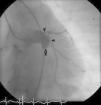

The patient was referred for a diagnostic cardiac catheterization. Angiography confirmed a coronary fistula measuring 13 mm in diameter at the aortic end and draining into the right atrium (RA) through at least two small openings (Figure 1). The left anterior descending (LAD) and circumflex (Cx) arteries originated in the proximal extremity of the fistula through two separate orifices. Catheterization showed normal right and left heart pressures, oxygen saturation step-up in the right atrium and Qp:Qs of 1.7. Informed consent was obtained and percutaneous closure of the fistula was attempted using a 16 mm Amplatzer® vascular plug II (AGA Medical). Through a femoral approach, a 7 Fr venous and a 6 Fr arterial sheath were used. A 6 Fr Concierge Amplatz Left 2 guiding catheter was positioned in the aorta at the fistula entrance and a 0.035 in Terumo® hydrophilic guide wire was advanced along the fistula, until the right atrium was reached. The wire was then snared and an arteriovenous (AV) loop was created. A 7 Fr Amplatzer Delivery System was used to deploy the device through the atrial end (Figure 2). A significant residual shunt was observed after deployment of the device. Cardiac enzymes were within normal range and the ECG showed no abnormalities. After this procedure anticoagulation was prescribed for six months and aspirin maintained thereafter.